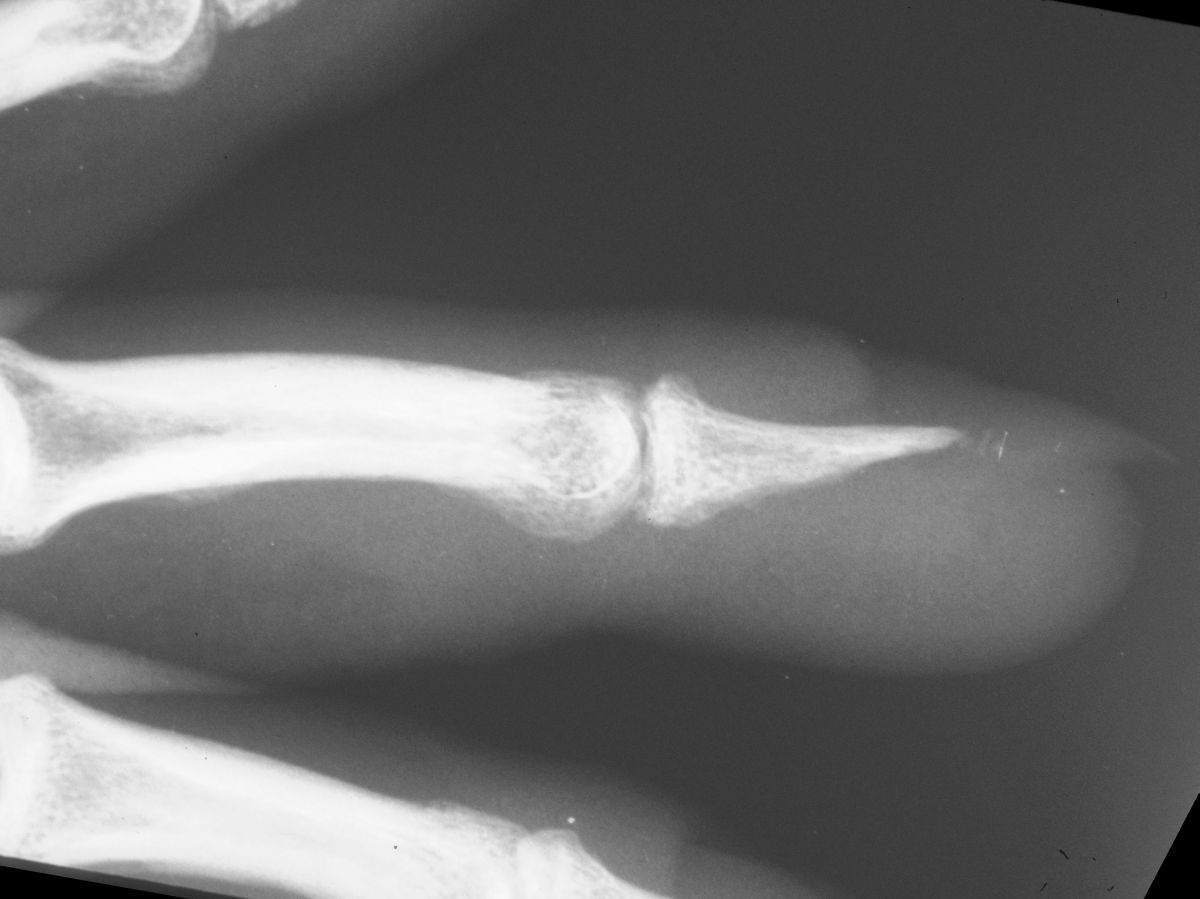

| Case

4. A dog bit off this young man's index fingertip. Although the PA Xray looks as though the bone was kept, additional views show an amputation through the tuft. |

| The defect. |